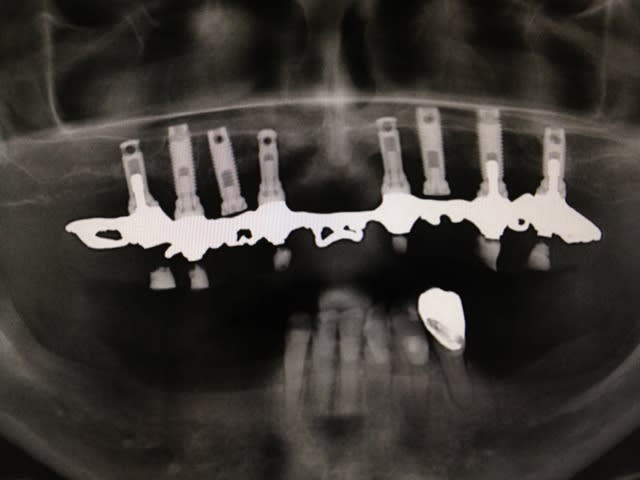

Implants posés autour de 1987,

complet transvissé acrylique sur structure en "or"

2 des implant sonts non-utilisés...

Patient veux refaire le haut.

Elle affirme que c'est du "Branemark"

La question, c'est quoi c'est implants, et les lisses ?

C'est des branemark mkII et des IMZ impactés.

Nobel MK (peu importe...hex externe) et les lisses doivent être des steri-oss (racheté par Nobel...)

Il est possible que ce soient tous des steri oss car ils avaient également des impactés ce qui ne change rien pour construire la prothèse tu vas probablement avoir un connection hex externe de 0,7 mm pour des régular et de 1mm pour des narrow ou des wide: